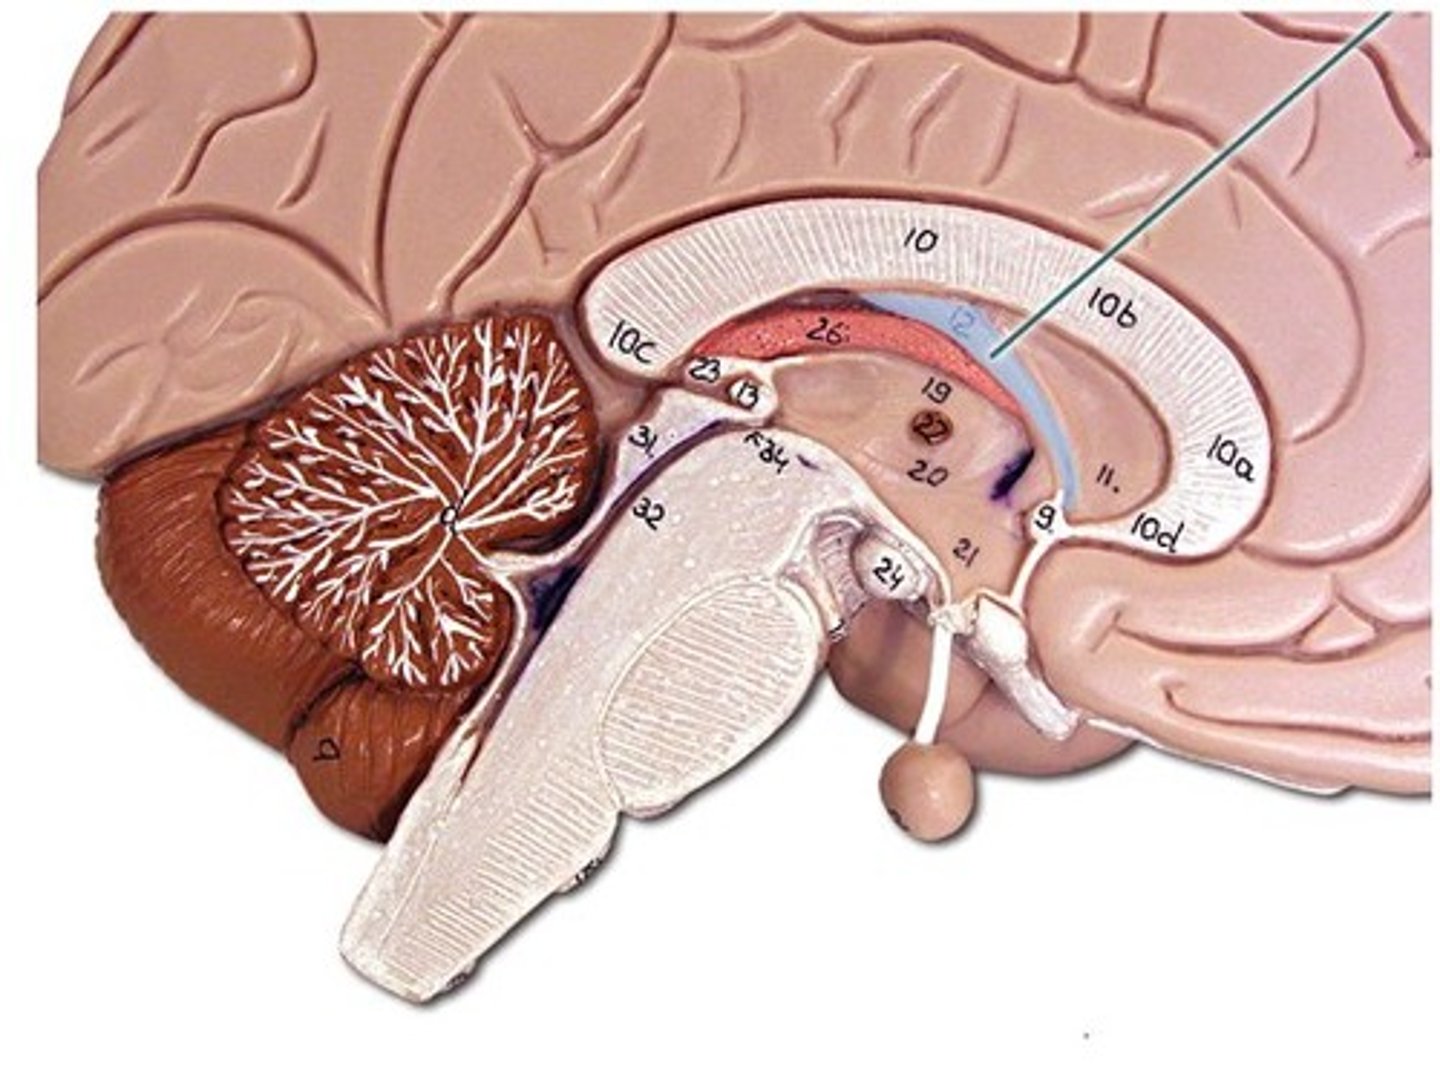

ventricles

cavities in the brain. Includes lateral ventricles - right and left, third ventricle, fourth ventricle, cerebral aqueduct, and choroid plexus.

lateral ventricles (left and right)

right and left. Actual open space. Behind the corpus collosum.

- Cerebrospinal fluid circulates through these ventricles and underneath the meninges.

third ventricle

in the area where the hypothalamus is.

fourth ventricle

located beneath the arbor vitae in the cerebellum.

cerebral aqueduct

connector between third and fourth ventricle in front of colliculi.

choroid plexus

ependymal cells - line ventricles and central canal of spinal cord.

meninges

scalp, periosteium, then, 1st meningeal layer. Includes dura mater, arachnoid mater, and pia mater.

dura mater

2 layers. Periosteal layer (outer layer) and the meningeal layer - closest to next meningeal layer. This can create the dural venous sinus. right below 1 in this picture

arachnoid mater

meningeal layer on top. 2 in this picture

pia mater

sits directly on top of brain tissue. When CSF circulates, it circulates on top of brain tissue. If you try to tear pia mater away, you'll tear brain tissue. 3 in this picture

corpus collosum

part of the cerebrum. white matter. Myelinated Axons. It's job is to allow communication between the left and right hemispheres.

fornix

connects the hypothalamus and the hippocampus.

thalamus

receives and filters incoming sensory information. All the senses except for smell hit thalamus first. With generalized and specified senses.

interthalamic adhesion

in the center of the thalamus. It connects the thalamus in the right and left hemisphere of the brain.

hypothalamus

mammillary bodies

two bumbs between pituitary gland and brain stem. Part of limbic system. Contributes to functioning of limbic system.

pineal body

considered an endocrine gland. Secretes melatonin. Plays a role in circadian rhythm - regulation of this. Sleep/wake cycles or night/day cycles. They don't know exactly how this works, but if the pineal gland does not release melatonin, you can have differences in circadian rhythm.